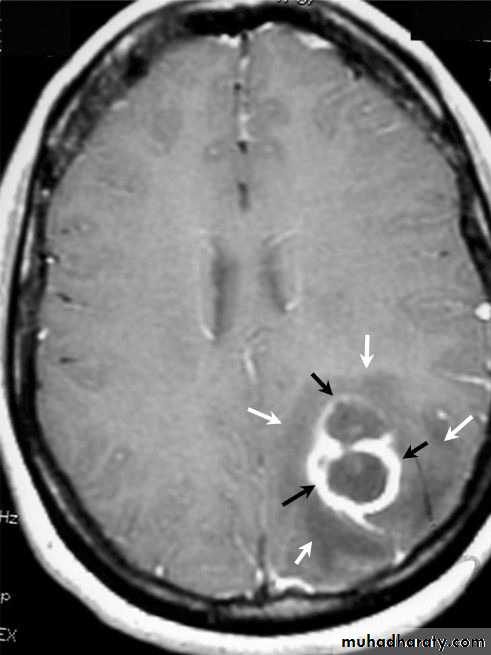

Brain Abscess MRI

Neurosurgery

• They will show a single (or multiple) space occupying lesion that is well delineated with an enhancing wall, with variable surrounding oedema.